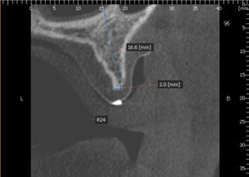

![]() |

| Phim X quang cắt lớp 3 chiều |

Kiểm tra mật độ xuơng ổ R24 trên phim CT 3 chiều và phần mềm cấy ghép Implant

| Xác định chiều rộng và chiều dài xuơng ổ răng |

Chiều dài: 16.6mm

Chiều rộng: 2.0mm